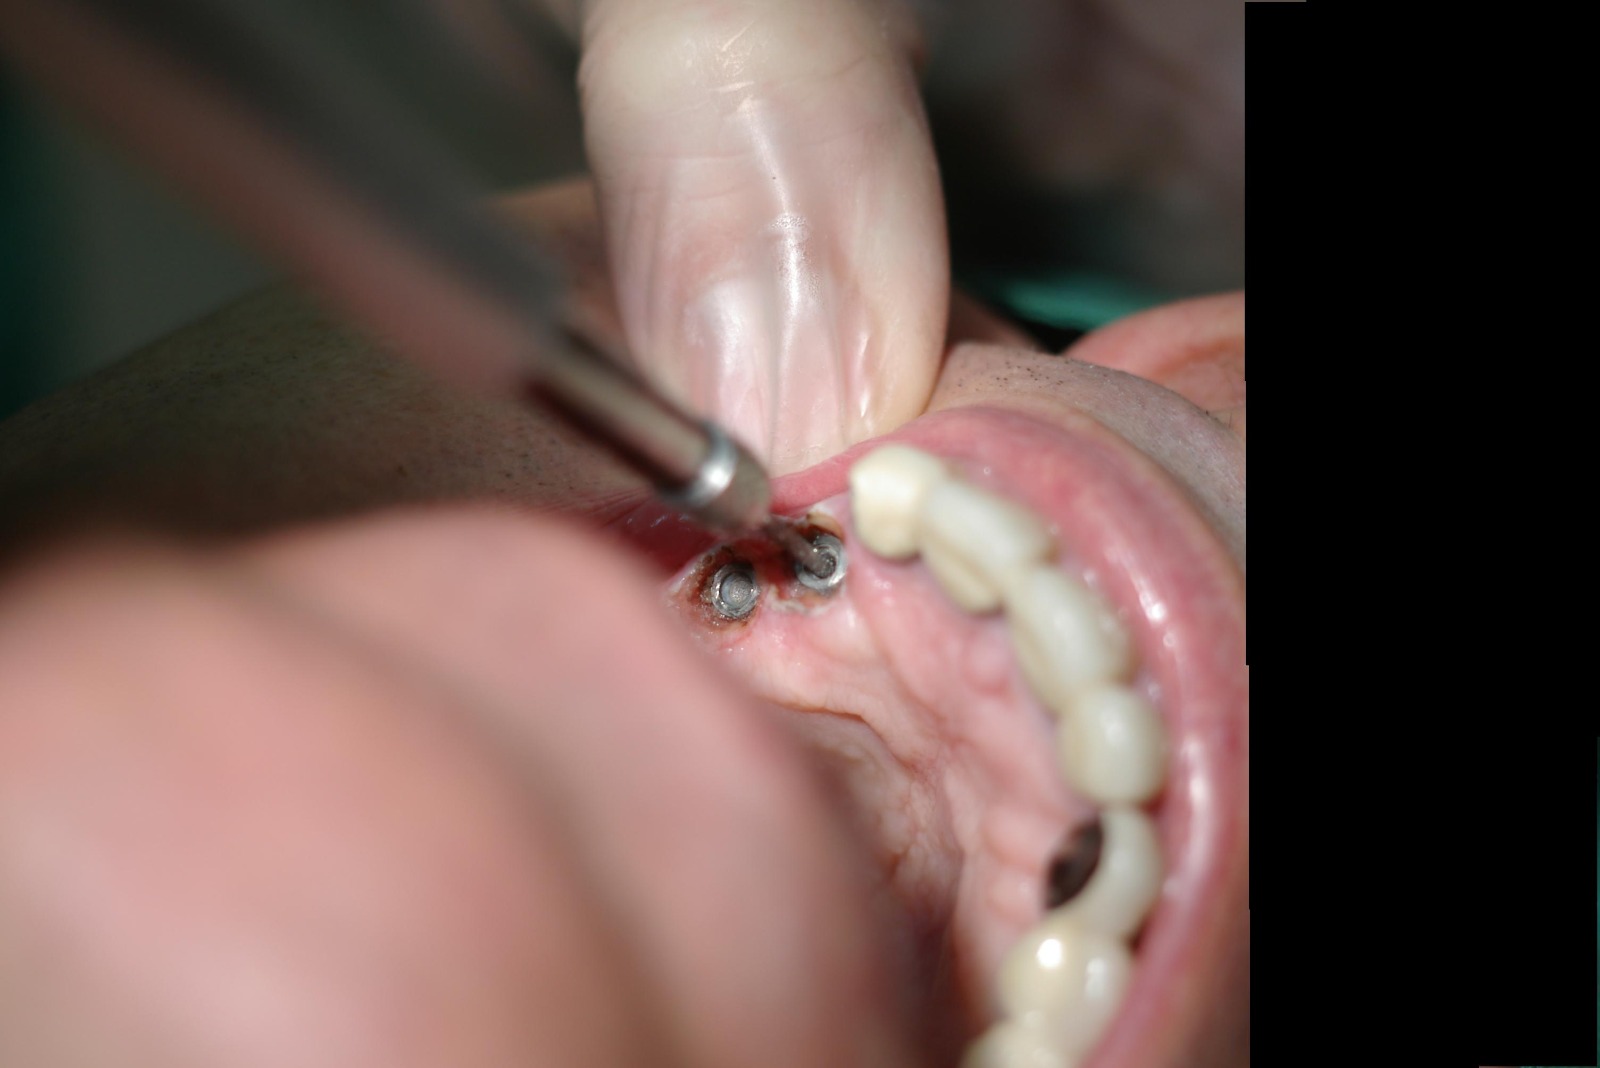

Actualmente vuelve el paciente de nuevo con la misma prótesis. Había roto dos de los tres pilares en concreto los más distales. El primero de los dos había roto la rosca del aditamento dentro del implante como ocurre habitualmente. Pero el ultimo pilar había roto directamente la cabeza del implante tal como se ve en la radiografía y lo que quedaba era un cilindro de titanio macizo perfectamente integrado en el maxilar, sin posibilidad de enroscar nada. Le explicamos al paciente que habría que quitar y poner un implante en el mismo acto. El paciente dijo que no, así que decimos que no se haría cirugía. Buscamos solución alternativa: hacemos un un agujero en el centro del macizo cilíndrico del implante roto y pasamos sucesivamente el set de machos roscantes. Utilizamos una fresa cañón de 1 mm que poco a poco se va introduciendo hasta 8mm con un poco de vagación, que hace que sea un poco mas de 1mm de diámetro. Posteriormente pasamos el conjunto de machos roscantes de métrica 2mm para poder usar un aditamento experimental, que era un palo de rosca de diámetro 2 mm unido a un cuerpo metálico en forma de sombrero napoleónico fabricado en cromo/cobalto, prototipos primitivos de la sistemática ASATIM y que tienen la característica de tener gran resistencia a la fractura. Nos llevó un tiempo largo el tallado de dichos aditamentos, tal como se puede observar en las imágenes, y tras cicatrizar la encía se le hizo una prótesis estándar. Esperemos que no lo rompa más veces.